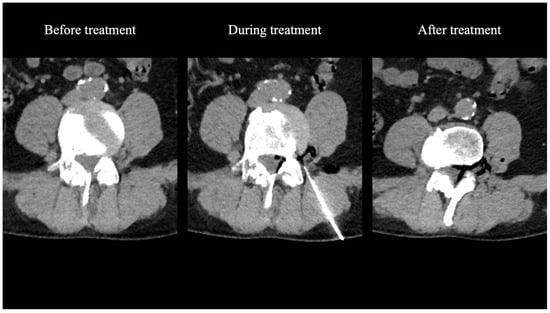

3.1. Procedural Technical Outcome

- Giurazza, F.; Guarnieri, G.; Murphy, K.J.; Muto, M. Intradiscal O2O3: Rationale, Injection Technique, Short- and Long-term Outcomes for the Treatment of Low Back Pain Due to Disc Herniation. Can. Assoc. Radiol. J. 2017, 68, 171–177. [Google Scholar] [CrossRef]